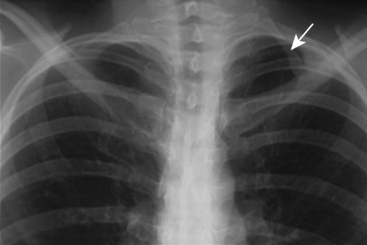

- Doctors make the diagnosis with a chest x-ray.

A rib fracture is a break or fracture in one or more of the bones making up the rib cage. Fractures of the first and second ribs may be more likely to be associated with head and facial injuries than other rib fractures. The middle ribs are the ones most commonly fractured.

Why are rib fractures so painful?

Rib fractures are usually quite painful because the ribs have to move to allow for breathing. When several ribs are broken in several places a flail chest results, and the detached bone sections will move separately from the rest of the chest. Specialty: Emergency Medicine. MeSH Codes: